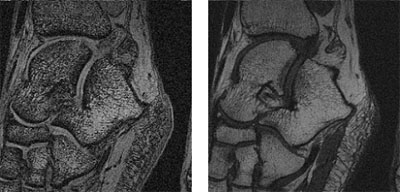

Innymi prowadzonymi badaniami była analiza zdjęć MRI przedstawiających poprzeczny przekrój przez ludzką stopę. Celem tych badań było określenie wpływu rozdzielczości tomografu oraz stosowanych sekwencji (Spin echo, Flash 3D) na teksturę kości śródstopia i pięty (rys. 8). Inne prace dotyczą segmentacji takich obrazów z wykorzystaniem sieci synchronicznych oscylatorów. Celem segmentacji jest wydzielenie obrazu kości pięty i śródstopia od pozostałych tkanek. Wynik segmentacji przykładowego obrazu pokazano na rys. 9. Potencjalnym zastosowaniem takich badań może być wspomaganie diagnostyki osteoporozy.

| Rys. 8 Obraz MRI poprzecznego przekroju przez stopę, zarejestrowany dla sekwencji Flash (a) oraz 3D Spin echo (b) |